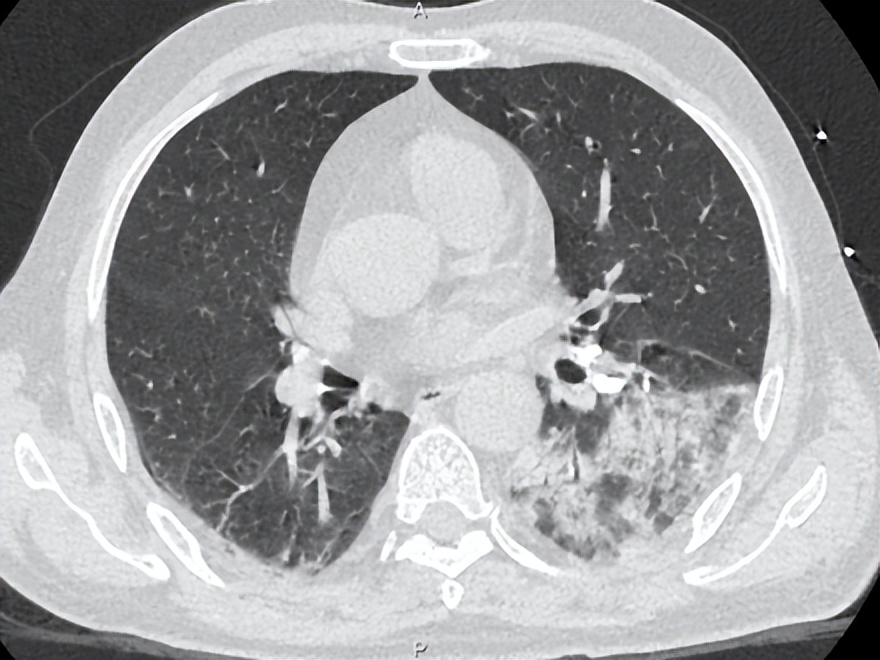

治疗后患者湿罗音减少,左肺可闻及Velcro啰音,7-6复查胸部CT如下:

考虑感染继发机化性肺炎,7.6加用泼尼松30mg po qd治疗机化性肺炎,继续多西环素0.1g bid治疗军团菌肺炎,并办理出院。

该患者的另一个临床特征是高PCT水平,据文献报道高PCT水平与需ICU治疗和高死亡率相关。 我们注意到,在病程中,PCT水平与体温未成平行下降关系,可能的原因为: 患者在入院初存在胃肠道症状和体征,包括腹泻、肠鸣音亢进。肠道作为细菌的蓄水池,此类患者可能存在肠道菌群移位。虽然没有相应的文献支持,我们在明确病原体为军团菌后,仍然将美平保留到7月2日,与多西环素重叠使用3天,直至PCT下降到安全范围。尽管在多西环素介入后, 6月30日床边胸片提示病灶较前明显增多,左肺大片浸润影,考虑到患者重症肺炎以及多个死亡相关预后因素存在,加用利福平5天联合抗军团菌。 患者在有效抗感染治疗基础上,7月6日复查胸部CT提示机化表现 ,氧合改善欠佳,给予短程激素应用,7月14日复查胸片提示病灶显著吸收。1个月后电话随访,患者原有咳嗽、气促等症状消失。